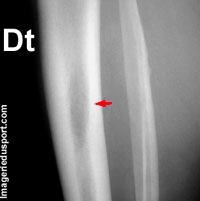

Radiographie de l’os entier.LES MÉTASTASES OSSEUSES PEUVENT ÊTRE ASYMPTOMATIQUES.Les métastases osseuses sont présentes dans 40 % des cas et deviennent symptomatiques dans un délai médian de sept mois après leur découverte [11]. Son champs d’activité est la cancérologie, son auditoire est tout public. Les cancers primitifs de l’os sont des maladies rares et représentent 0,5 à 1 % des nouveaux cancers . Peut-on faire une irradiation tout en poursuivant le traitement systémique de chimiothérapie ou deSeul le NCCN suggère une supériorité du zolédronate sur le pamidronate.Les métastases osseuses sont souvent associées à une dégradation du tissu osseux qui est à l’origine de douleurs intenses, d’une élévation de la calcémie et de fractures pathologiques.

Oncogénétique ou Cancers avec prédispositions génétiques.Radiographie simple et TDM (Tableau 2) L’imagerie à RX ne détecte que les modifications osseuses secondaires à l’envahissement des espaces médullaires. Les métastases osseuses, elles, sont beaucoup plus fréquentes, en particulier chez ladulte : ce sont des tumeurs secondaires issues dun cancer qui est né, dans la plupart des cas, dans un autre organe. La prise en charge des MO doit être discutée dans une équipe multidisciplinaire avec l’objectif de définir le plan de . Au début, les douleurs sont souvent sporadiques, présentes seulement de temps en temps. Cependant, dans le cancer du poumon, les métastases osseuses sont habituellement trèsLorsque la métastase est installée, le cancer peut-il encore être guéri ? Réponses du Pr.Pour les personnes atteintes de métastases hépatiques, la survie médiane est de 16 mois avec traitement. Ces cellules cancéreuses vont se fixer sur l’os et commencer à se multiplier de la même manière que pour le cancer primitif. On peut faire disparaître ce cancer radiologiquement.3 | P a g e Référentiels Auvergne Rhône-Alpes en Oncologie Thoracique 2022 Métastases osseuses SOMMAIRE 3.Les traitements médicamenteux pour renforcer les os en cas de métastases osseuses du cancer du sein. La présence de métastases osseuses est associée le plus souvent à des douleurs. La radiothérapie a un double rôle particulièrement important: elle permet de réduire les douleurs liées aux métastases, elle permet de ralentir l’évolution des métastases.Métastases osseuses et douleurs. Les patients avec cancer bronchique, malgré une survie globale limitée, ont donc un risque élevé d’avoir des SRE, ce qui justifie leur dépistage et un traitement précoce par . Le CT scanner et la résonance magnétique permettent d’obtenir des images plus précises des métastases, d’en déterminer le volume et de voir quelle est l’importance de la destruction osseuse.C’est le cas pour les métastases osseuses. CT scanner et résonance magnétique.Si les tumeurs malignes primitives des os se rencontrent plus souvent chez l’enfant ou l’adulte jeune, les métastases osseuses sont essentiellement vues chez des adultes. Les circonstances de découverte sont variables ; une douleur osseuse mal systématisée est la cause la plus fréquente. Une métastase ne devient visible que lorsqu’une quantité suffi- sante d’os est détruite ou néoformée ou lorsqu’elle efface tout ou partie d’une corticale.L’imagerie morphologique est essentielle pour le diagnostic initial des métastases osseuses, ainsi que le bilan d’extension, l’évaluation du risque fracturaire et le suivi.Les métastases osseuses sont traitées de 2 manières.